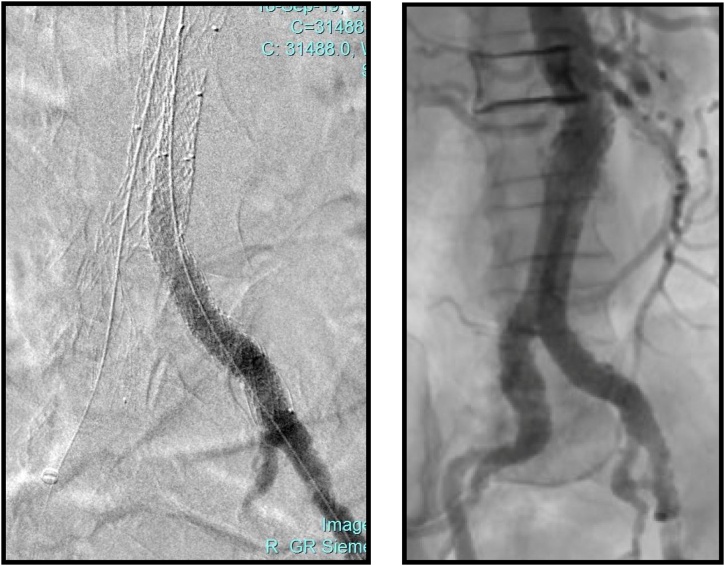

Fig. 2.

The final angiogram images of our patient after balloon expandable covered stents deployment crushing the left iliac extension stent graft of EVAR.